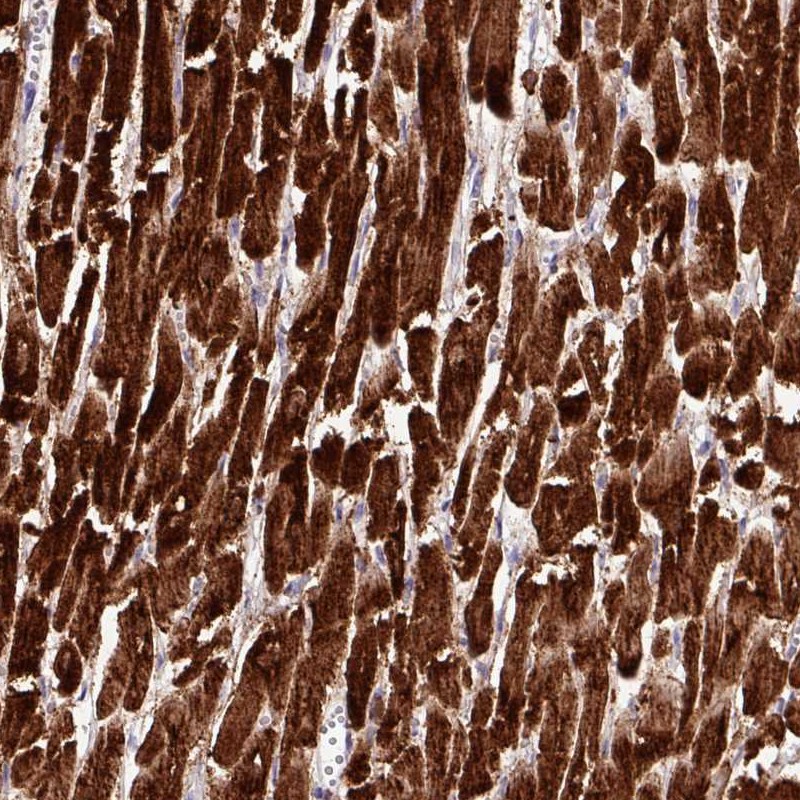

Immunohistochemistry analysis in human heart muscle and lymph node tissues using Anti-CKMT2 antibody. Corresponding CKMT2 RNA-seq data are presented for the same tissues.